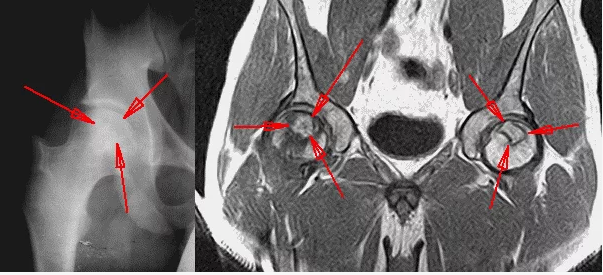

Степени аваскулярного некроза

Степени аваскулярного некроза 116 фотографий